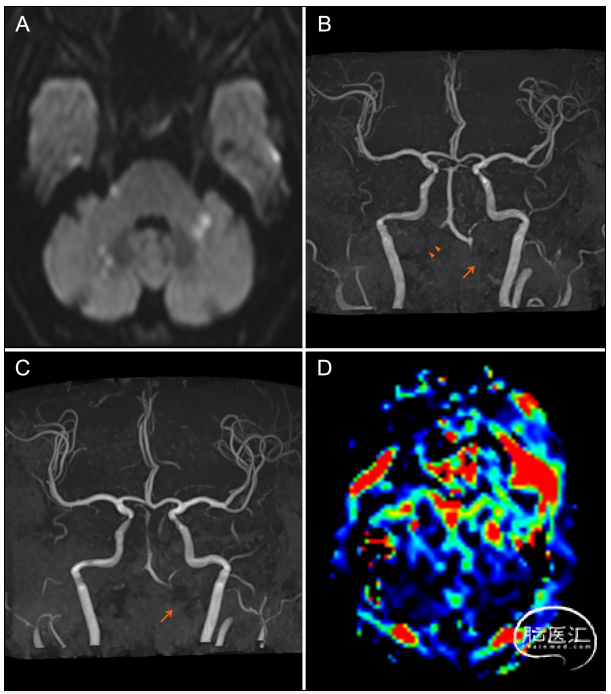

71岁男患,既往高血压、糖尿病、房颤、风湿病史,突发头晕和构音障碍来诊。查体:右侧眼睑下垂、共济失调。影像学检查见图1,给予阿司匹林+氯吡格雷双联抗血小板治疗,患者仍有症状进展,入院22天复查MRI及灌注见图1,入院第23天行椎动脉球囊扩张成形术(图2),手术顺利,术后患者症状改善。术后经颞动脉活检确诊巨细胞动脉炎(GCA),继续双抗+糖皮质激素治疗,症状改善。术后6个月随访良好(图2)。

图1. A:入院MRI弥散可见双侧小脑半球及桥脑多发急性缺血灶;B:入院MRA提示左侧椎动脉V4段重度狭窄,右侧椎动脉闭塞;C:入院22天复查MRA提示病变进展,左侧椎动脉闭塞;D:入院22天CTP灌注可见小脑及脑干广泛低灌注表现。